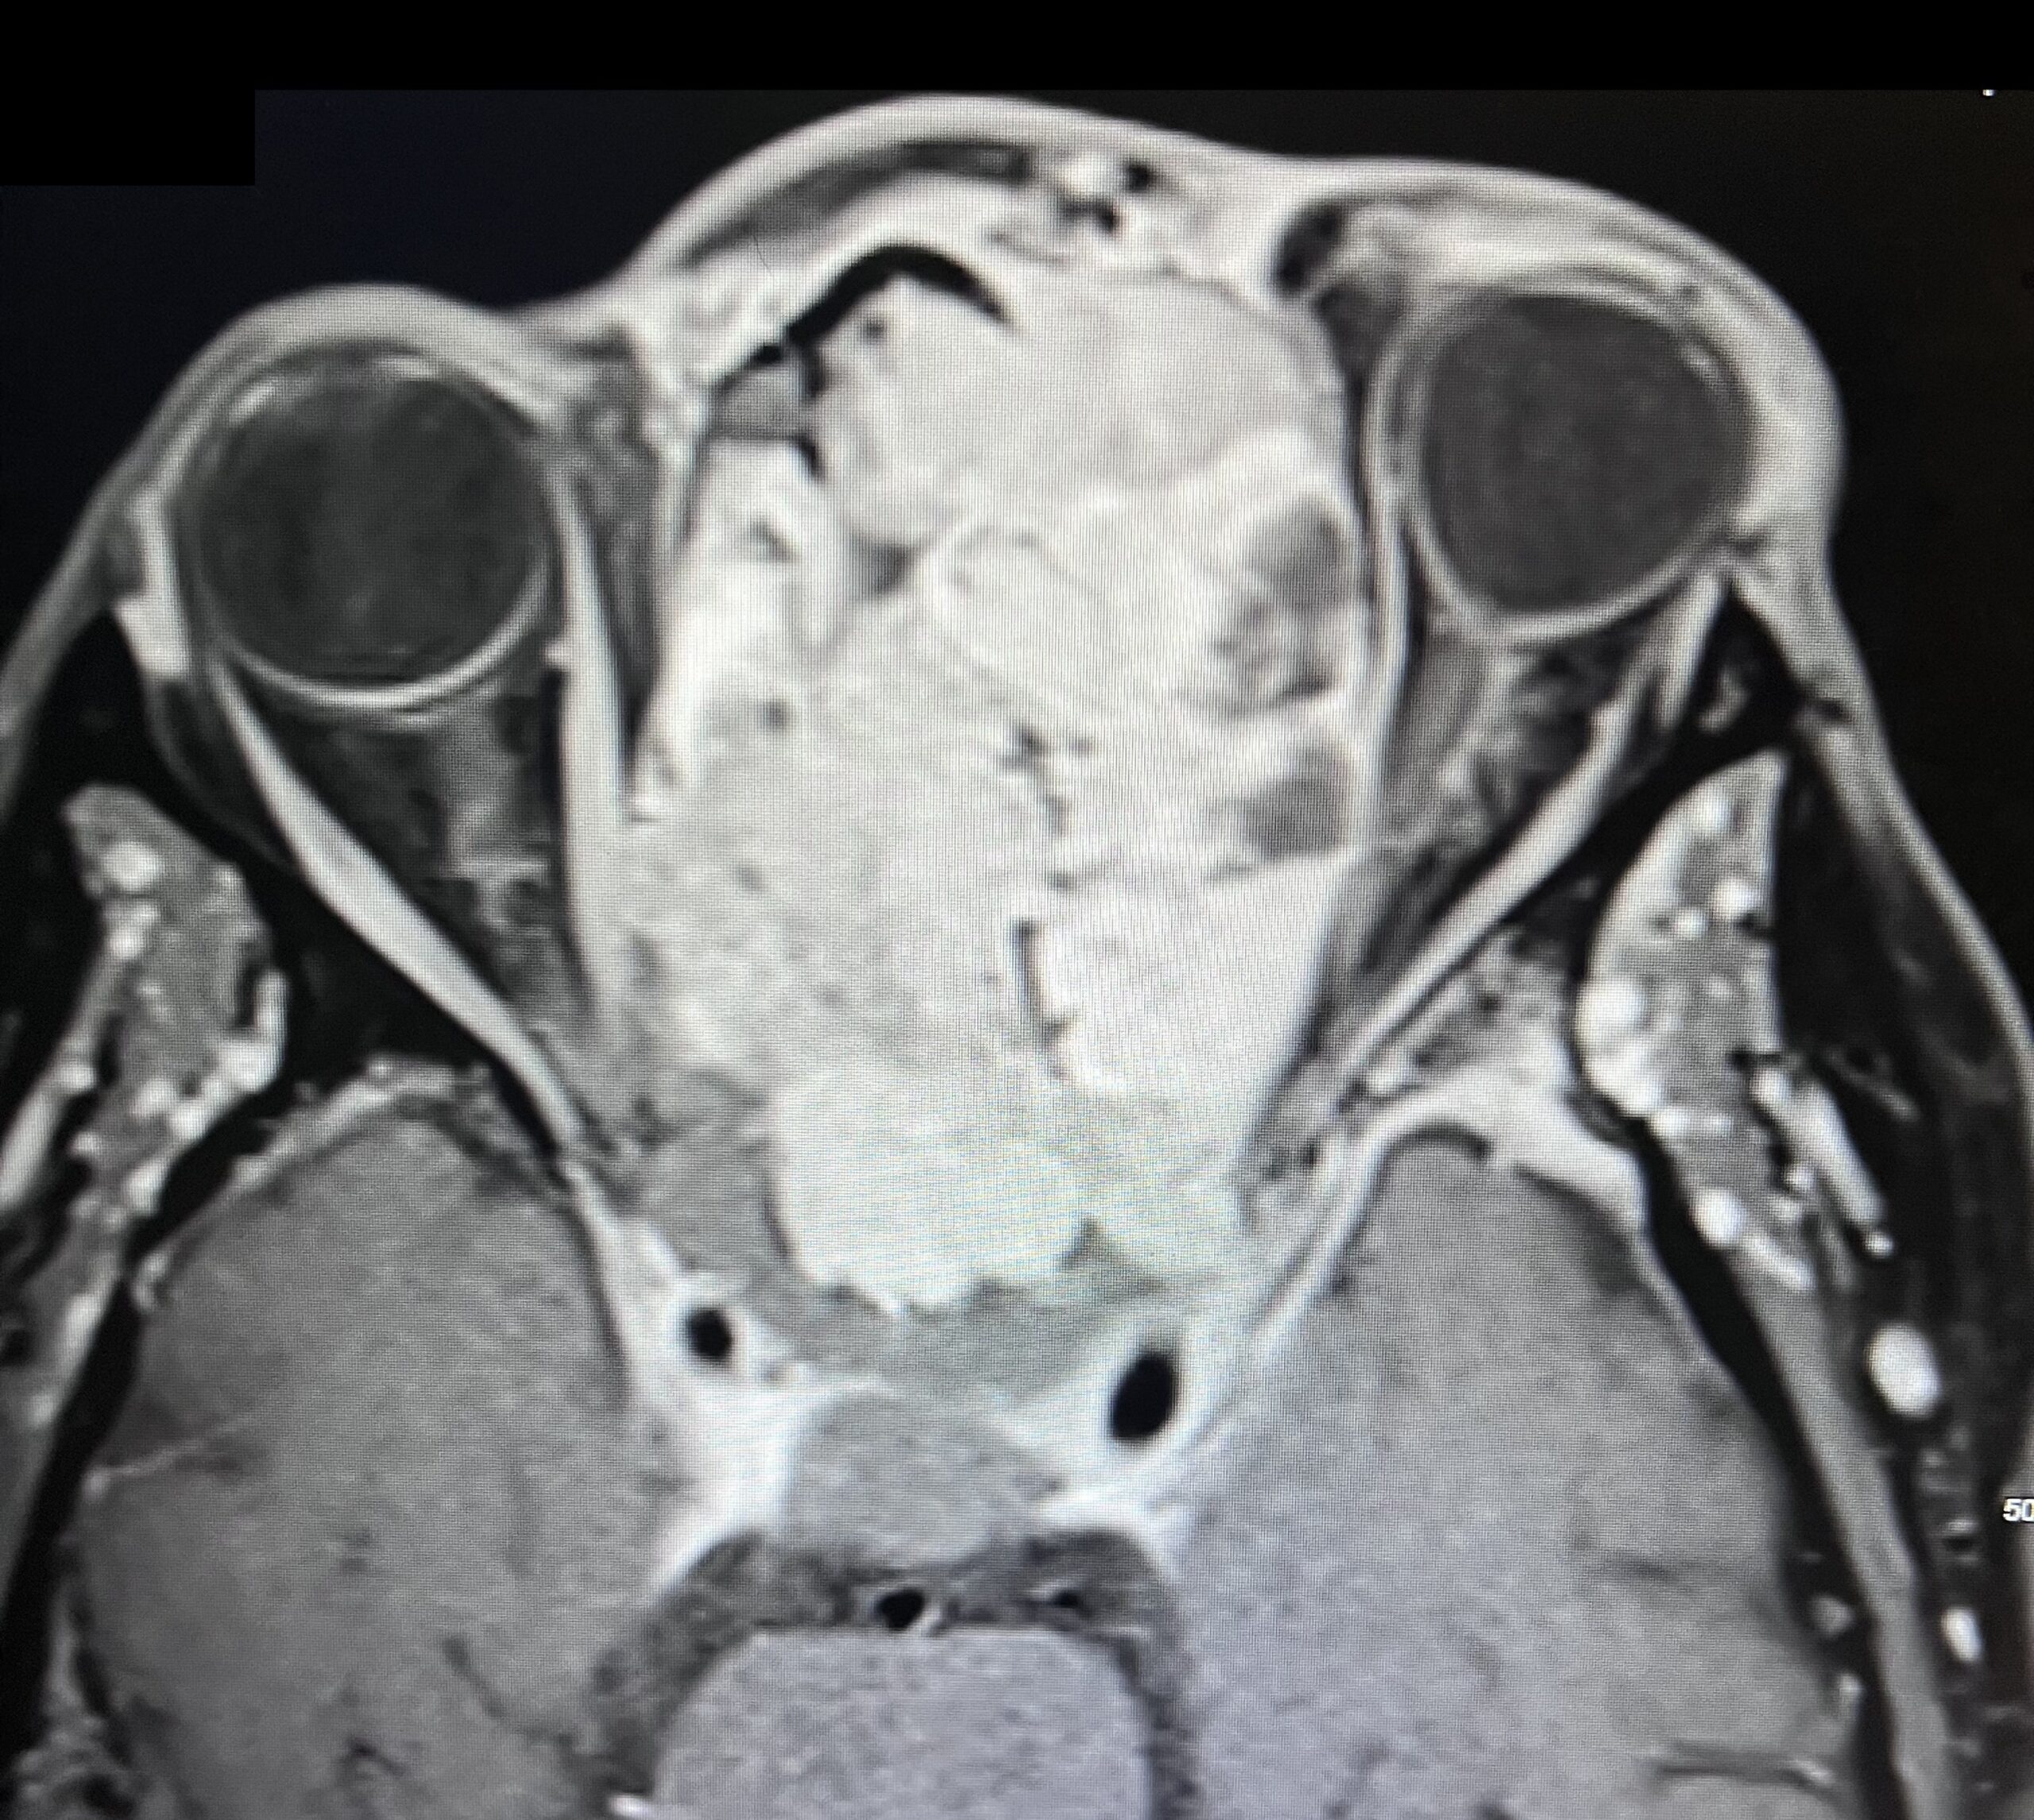

Sinonasal carcinoma is a rare malignancy that often presents with nonspecific symptoms, making early diagnosis challenging. Delayed recognition can lead to disease progression and worse outcomes. This case report emphasizes the importance of early identification, prompt imaging, and multidisciplinary management. A 73-year-old male with a history of anemia and hypertension presented with progressive facial swelling, 20-pound weight loss, and vision loss in the left eye over two months. Initially misdiagnosed with bacterial sinusitis, his symptoms persisted. Examination revealed a proptotic left eye and a large obstructive nasal mass. Computed tomography (CT) and MRI (magnetic resonance imaging) demonstrated a destructive sinonasal mass with skull base and intracranial extension. A biopsy confirmed sinonasal carcinoma, and the patient was started on chemoradiation therapy due to the inoperability of the tumor.

This case underscores the importance of recognizing red flag symptoms such as persistent facial swelling and neurological deficits. Multimodal imaging played a critical role in diagnosis. The literature suggests sinonasal carcinoma is often diagnosed late, reinforcing the need for early suspicion and specialist referral. Sinonasal carcinoma should be considered in patients with persistent facial or nasal symptoms. Timely imaging, biopsy, and interdisciplinary care are essential for optimizing outcomes.